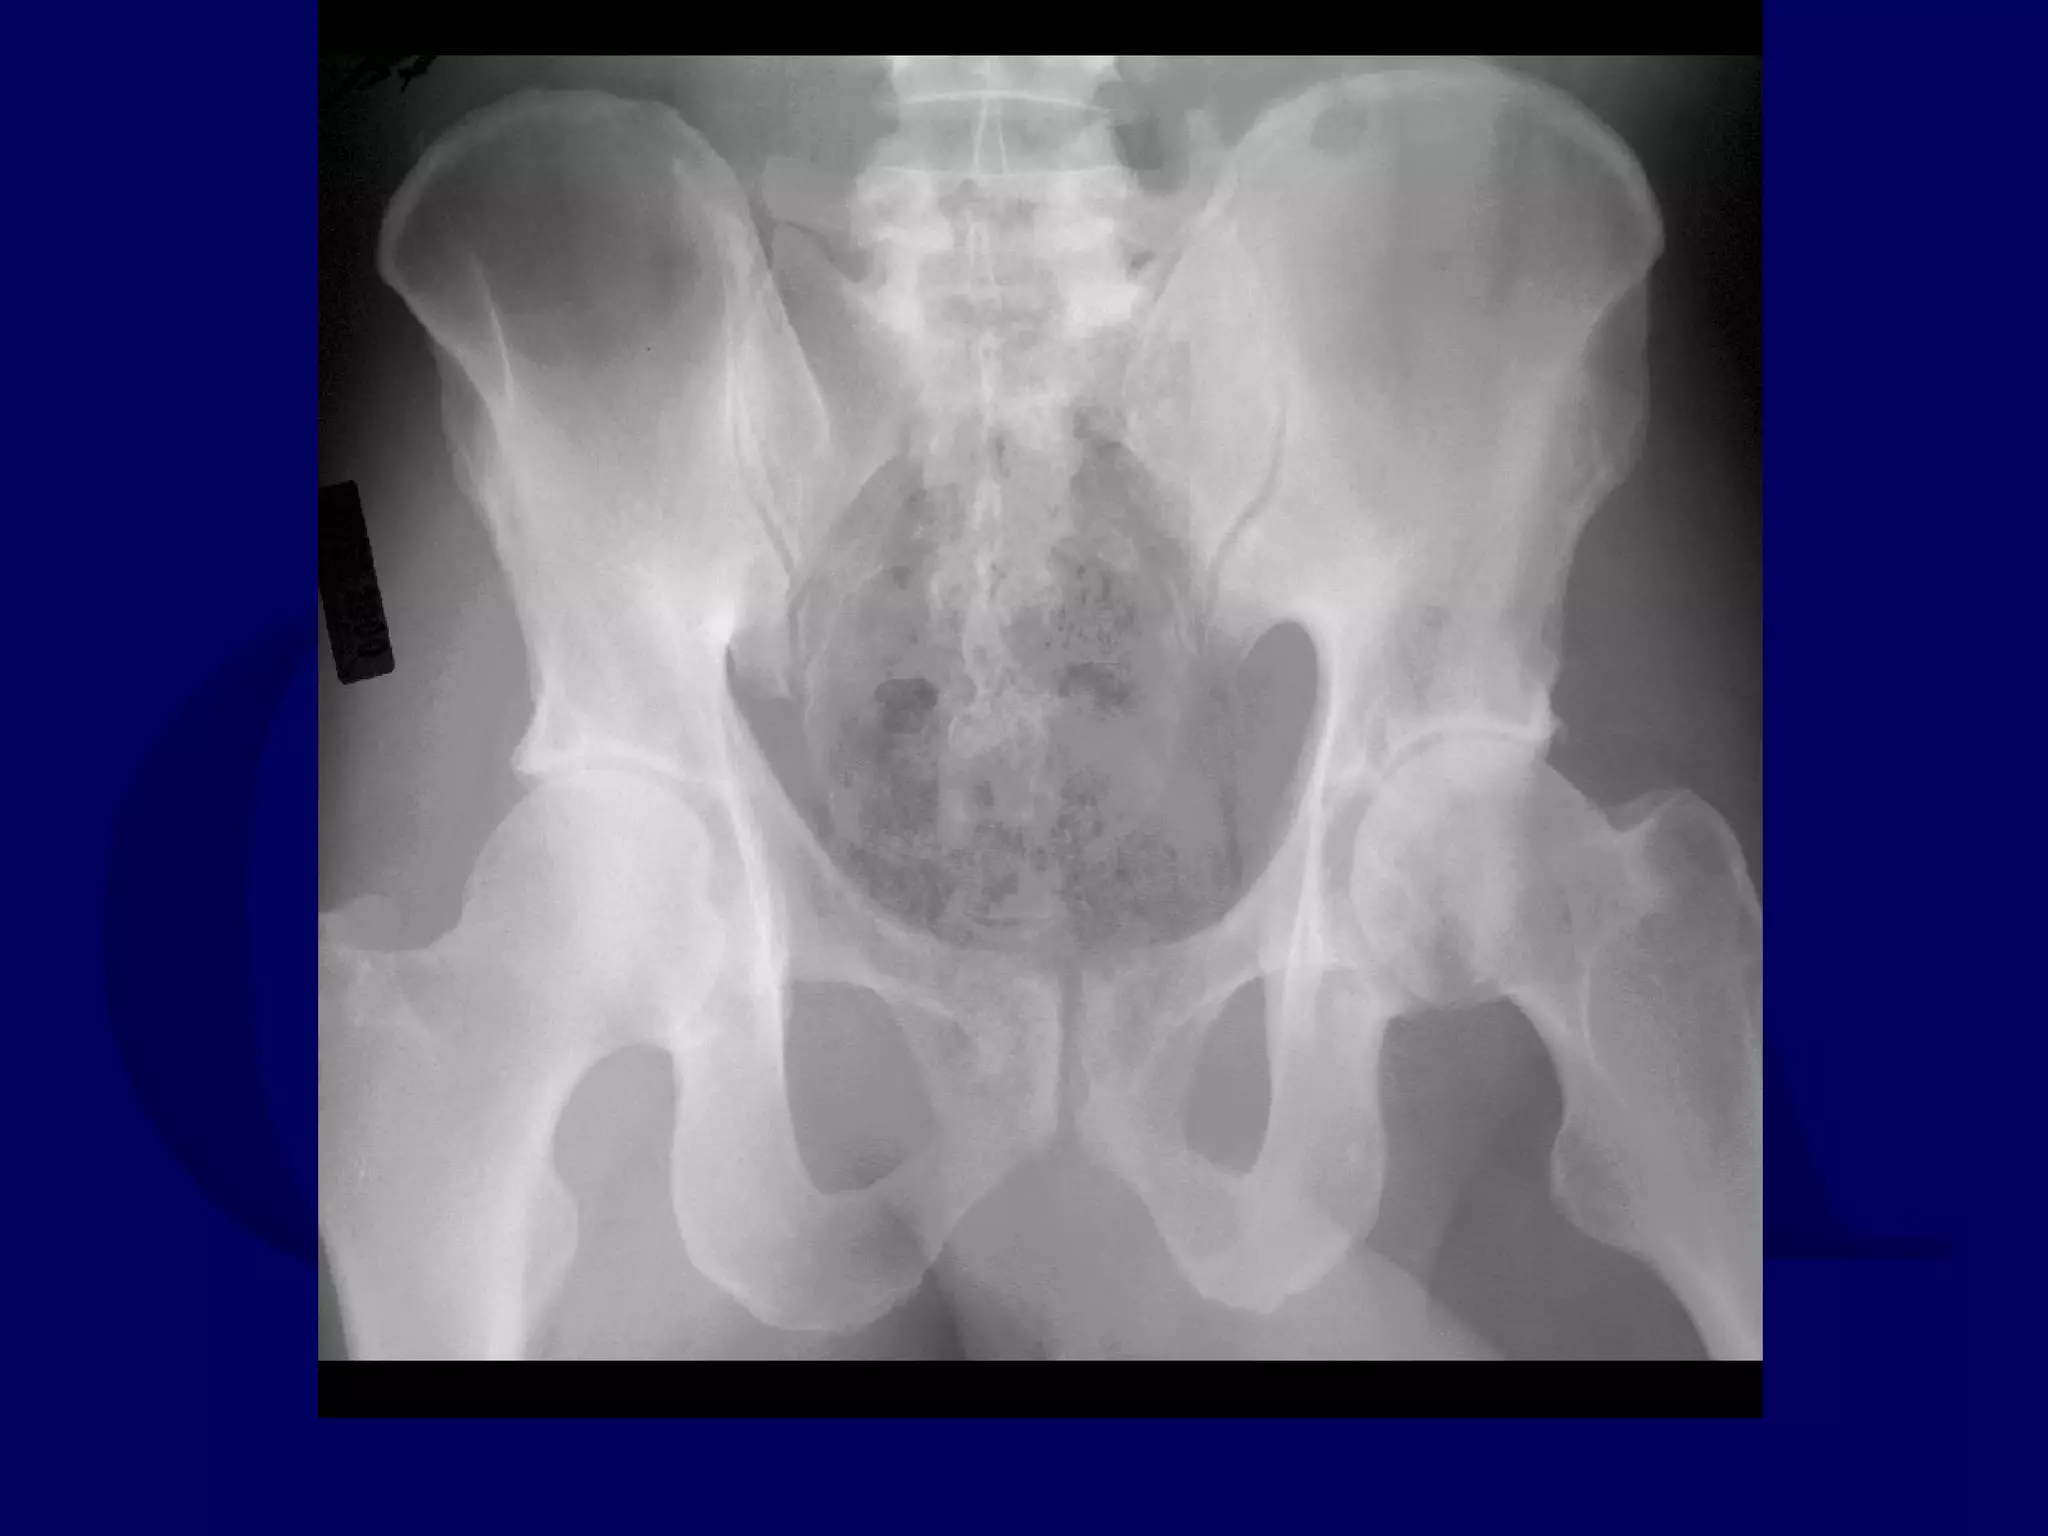

Avascular Necrosis

“In our opinion avascular necrosis is a diagnosis much too often

put forward to explain a post-operative complication. Since it is

known that there is nothing we can do about it, as the trauma is

considered solely responsible for it, there is much too great a

tendency to blame necrosis for what is really a wearing of the

femoral head against a malreduced fracture line. If wear takes

place there is disappearance of a segment of the head but no

sequestrum formation, and the shape of the loss of substance is

the negative imprint of the shape responsible for the wear: the

step in the acetabular reconstruction. For instance, wearing

against a transverse fracture line appears on the antero-posterior

view as an orange-slice-shaped missing part of the head without

any sequestrum.”